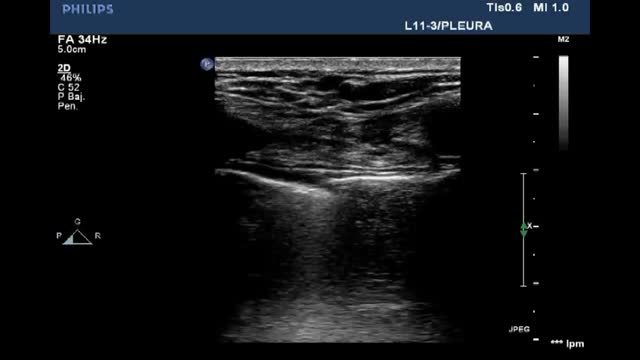

Pleural effusion (PE)Ultrasound assesses the volume (detecting millimetric magnitudes) and the characteristics of PE, guiding the site of puncture for evacuation of the effusion when needed. For this purpose, we ideally use a low-frequency convex probe (2.5-5 Hz), which sacrifices resolution in favor of greater ultrasound wave penetration capacity, reaching more in depth and visualizing the diaphragm and liver or spleen, and their relation to the lung parenchyma.

With the patient in the supine position, we place the probe on the mid-axillary line and locate the fundamental reference of the study: the diaphragm. All anechoic images above the diaphragm correspond to the chest cavity (pleural fluid). In contrast, such images located below the diaphragm correspond to the abdominal cavity (ascitic fluid)(Video 10).

Ultrasound signs related to pleural effusionPleural effusion is a genuine image, not an artifact. It is classically defined as an anechogenic component. The appearance of PE in critical patients is not always as described, however, since there may be coexisting hemothorax, complicated effusion and empyema, which are characterized by different degrees of echogenicity.

In terms of ultrasound exploration, PE is defined by the following signs:

Quad sign (Suppl. Fig. 8): This is a static sign defined by a quadrilateral image with regular margins. The upper margin corresponds to the parietal pleura, the lower margin to the visceral pleura, and the lateral margins correspond to the shadows of two consecutive ribs.

Sinusoid sign (Suppl. Fig. 8) (Video 11): This is a dynamic sign. In M mode it manifests as a sinusoid, reflecting the variation of the interpleural distance with the respiratory movements. In this regard, the distance is shorter during inspiration, while in expiration the two pleural layers are more separated. When the fluid is more viscous or shows septation, this sign may be absent.